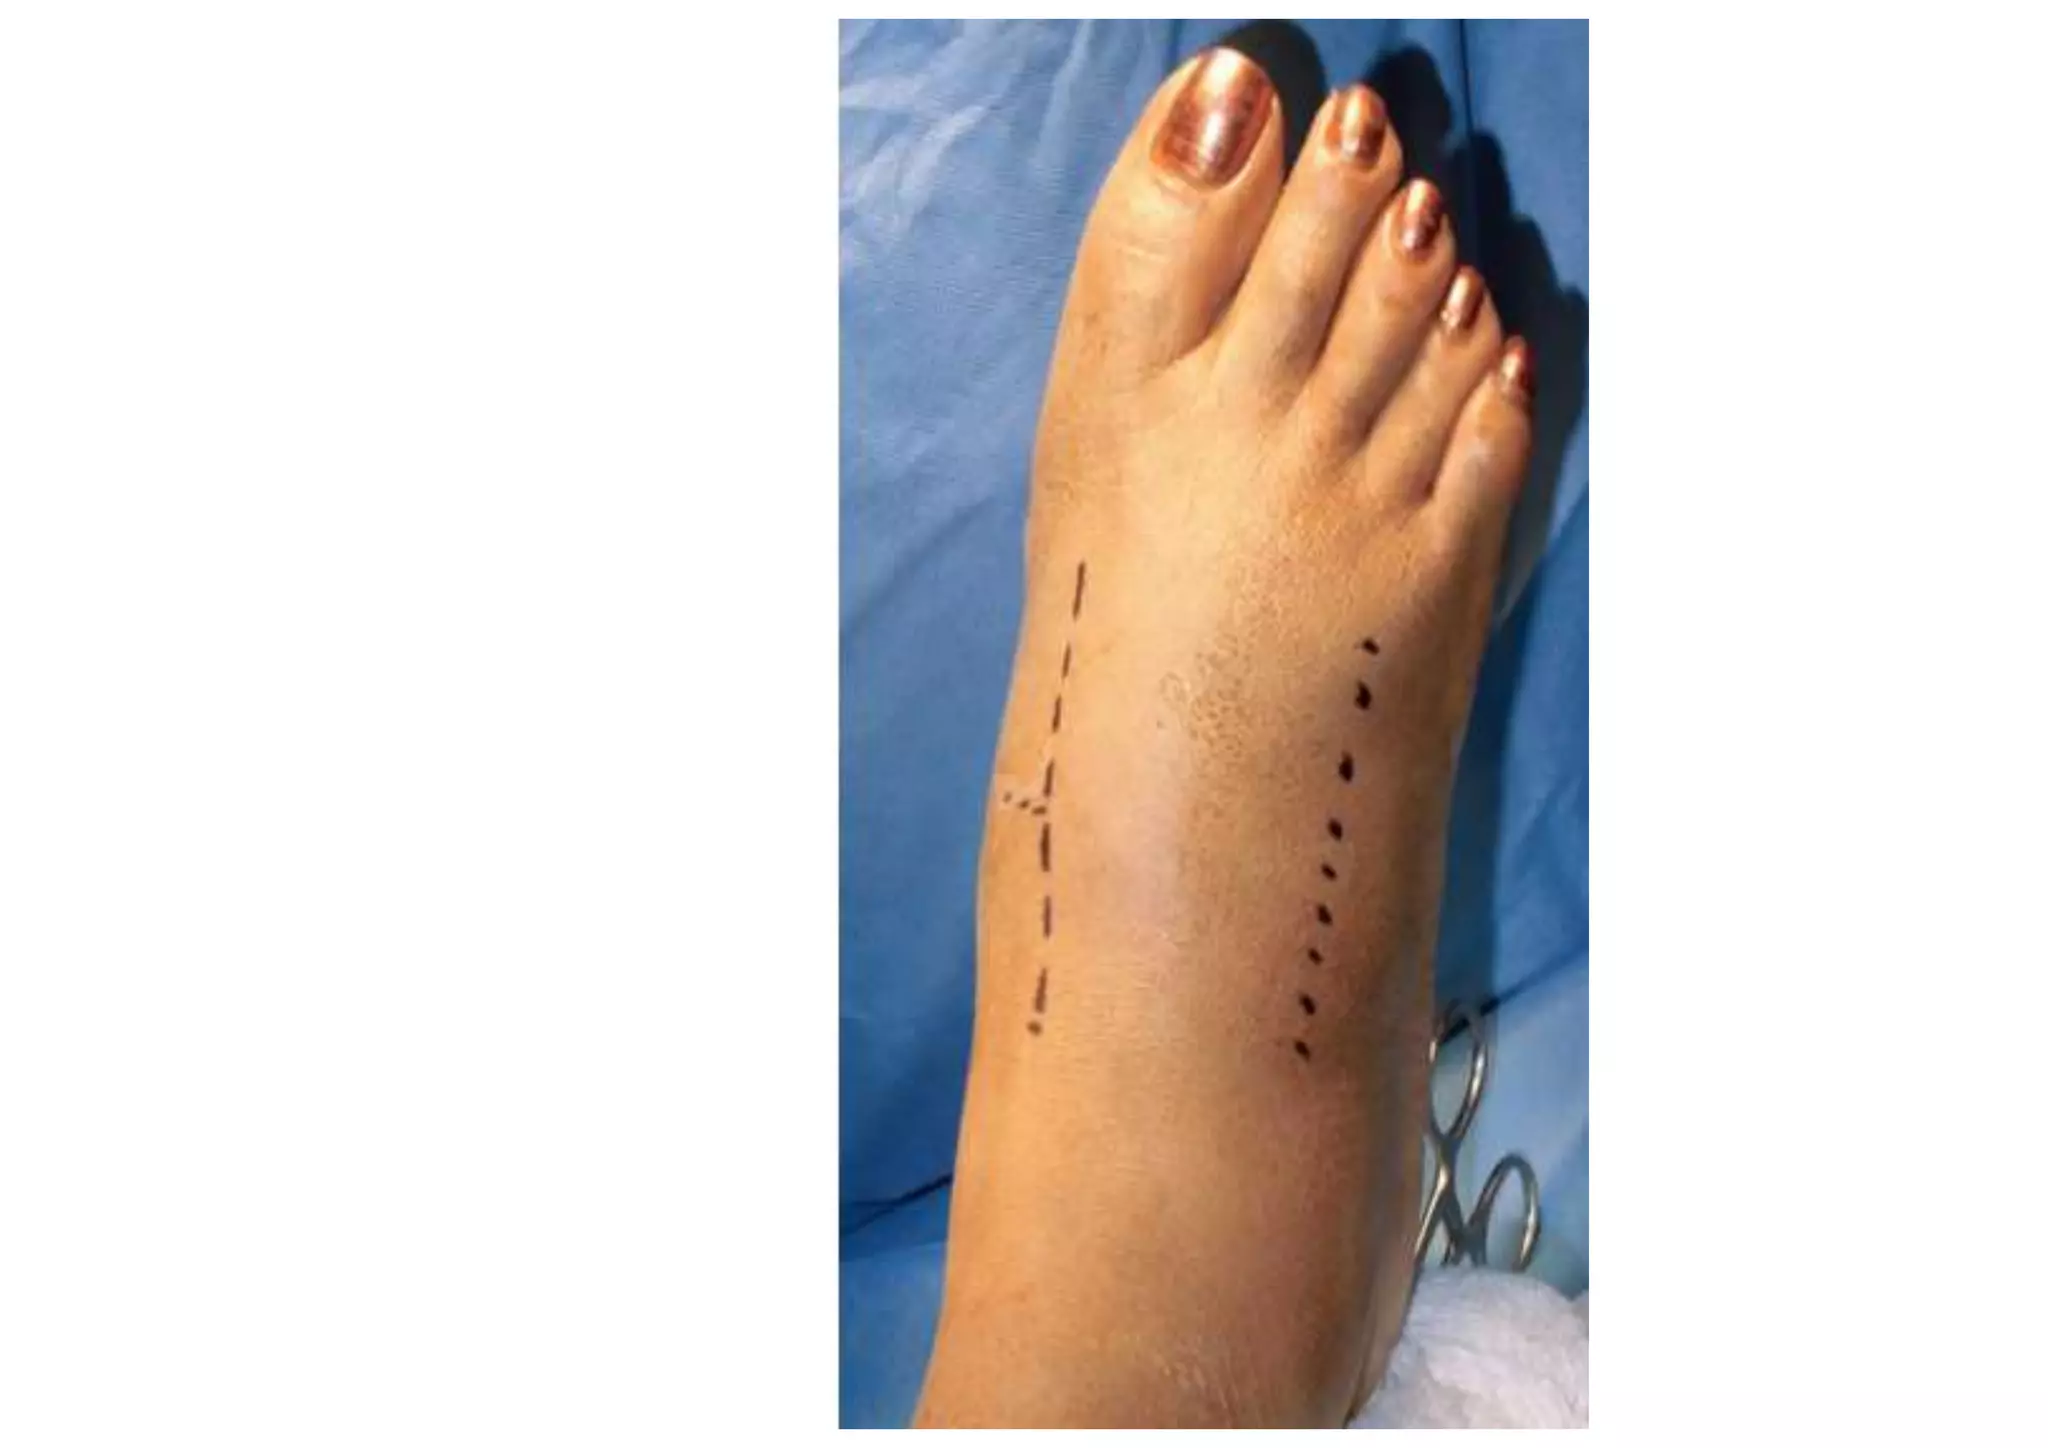

• The most common approach is using two

longitudinal incisions.

• The first is centered over the first/second

intermetatarsal space allowing identification

of the neurovascular bundle and access to

the medial two tarsometatarsal joints.

• A second longitudinal incision is made over

the fourth metatarsal

OPERATIVE MANAGEMENT • Thisshould be considered when displacement of the tarsometatarsal joint is >2 mm. • The best results are obtained through anatomic reduction and stable fixation. • The most common approach is using two longitudinal incisions.

• The firstis centered over the first/second intermetatarsal space allowing identification of the neurovascular bundle and access to the medial two tarsometatarsal joints. • A second longitudinal incision is made over the fourth metatarsal

• #31 ■ With the patient under a regional or general anesthetic, make a dorsal incision lateral to the extensor hallucis longus tendon over the interval between the base of the first and second metatarsals, slightly more lateral if access to the third tarsometatarsal joint is necessary. At the distal extent of the excision, preserve the most medial branch of the dorsal medial cutaneous nerve. ■ A second incision may be needed more laterally if open reduction of the fourth and fifth tarsometatarsal joints is necessary (Fig. 88-66A). ■ Locate and incise the inferior extensor retinaculum